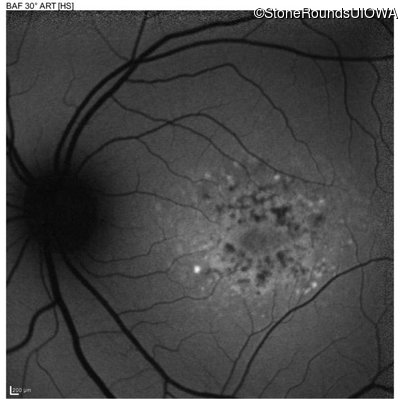

This 16 year old female first had difficulty seeing the blackboard at age 9. Her eye doctor at the time felt at the time that she was "faking it". More recently her eye doctor told her she would be blind by age 20 and suggested she get a seeing eye dog.

| AR Stargardt Disease | ABCA4 | Asp507Tyr GAT>TAT | IVS40+5 G>A | AR |